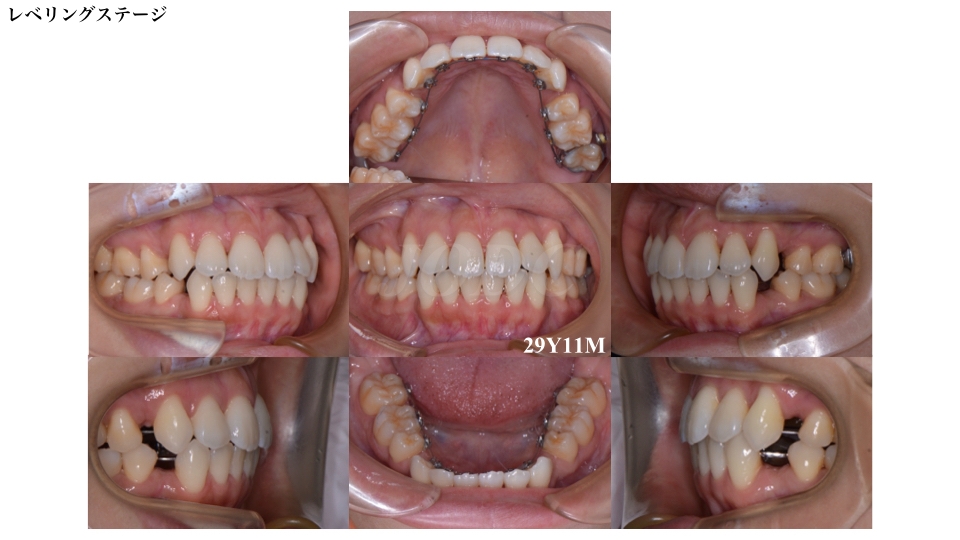

上下顎に装置を装着してから約7ヶ月後のレベリングステージ(歯のデコボコを改善しながら歯の高さを合わせる段階))ステージです。